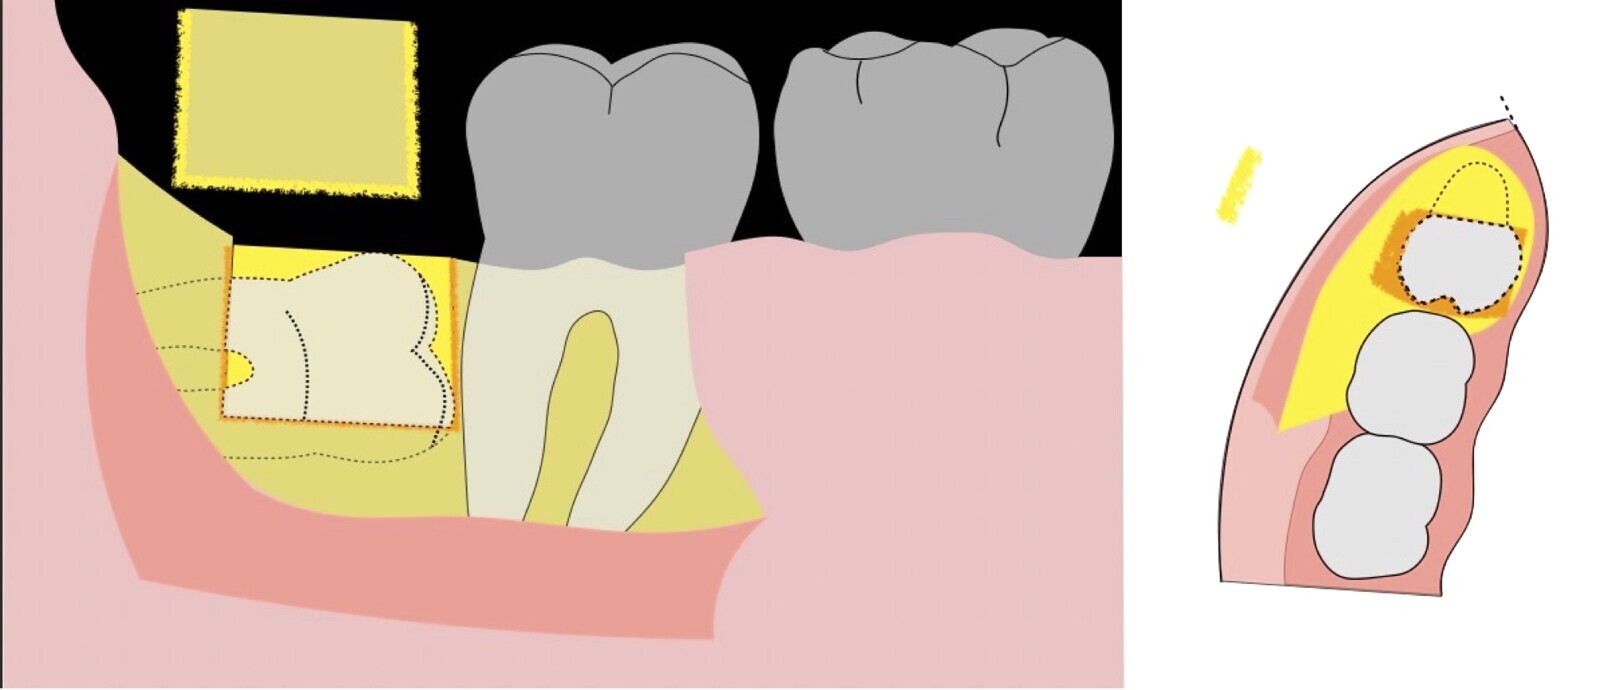

El procedimiento se inicia colocando anestesia troncular para bloqueo del nervio dentario inferior y sus ramas. Luego, se establecerá el diseño de acceso según la disposición de la molar a extraer. Para fines didácticos, se explicará cómo se realizaría la extracción de la molar de la Figura 1: se realiza una incisión horizontal a nivel de la zona retromolar hasta llegar a distal de la segunda molar, continuándose con una incisión intrasurcular hasta mesial de la segunda molar, finalizando con una incisión vertical a espesor total hasta llegar a la línea mucogingival (Figura 2).

Figura 2. Diseño de incisión para el acceso a la tercera molar.

Figura 3. Decolado a espesor total para el acceso a la tercera molar.

Figura 4. Demarcación de la zona de osteotomía con insertos de corte recto y/o angulado a nivel oclusal. Vista frontal (a). Vista oclusal (b).